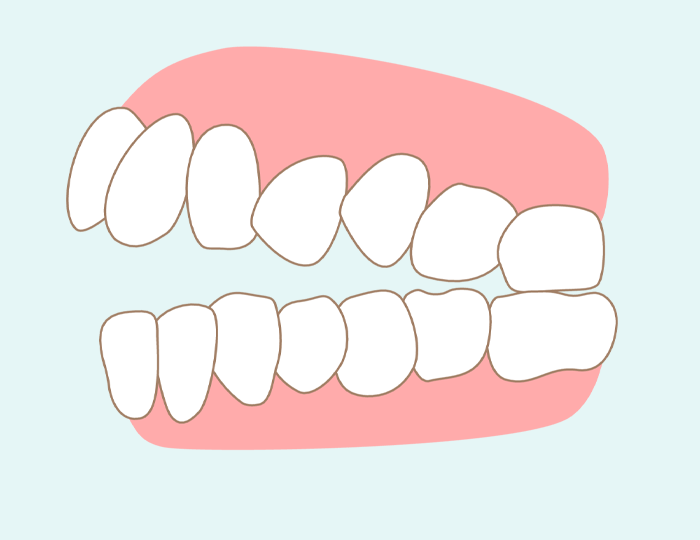

開咬

奥歯が咬み合っているのにも関わらず、上の前歯と下の前歯が噛み合わず開いている状態を、開咬(かいこう)、あるいはオープンバイトといいます。原因としては、指しゃぶりの期間が長いことや、舌を前に突き出す・前歯で舌を挟むくせがあるなどの後天的要素と、遺伝的に上顎と下顎の位置に異常がある先天的要素が挙げられます。

開咬は本来前歯にかかる力が全て奥歯にかかることから、早期に奥歯を失うリスクが最も高いと言われています。顎の関節の負担も大きく、顎関節症に悩まされる方も多いという問題もあります。その他にも、空気が抜けてしまい滑舌が悪くなりやすい、見た目に劣等感を抱く原因になるなど、不正咬合は様々な悪影響をもたらします。